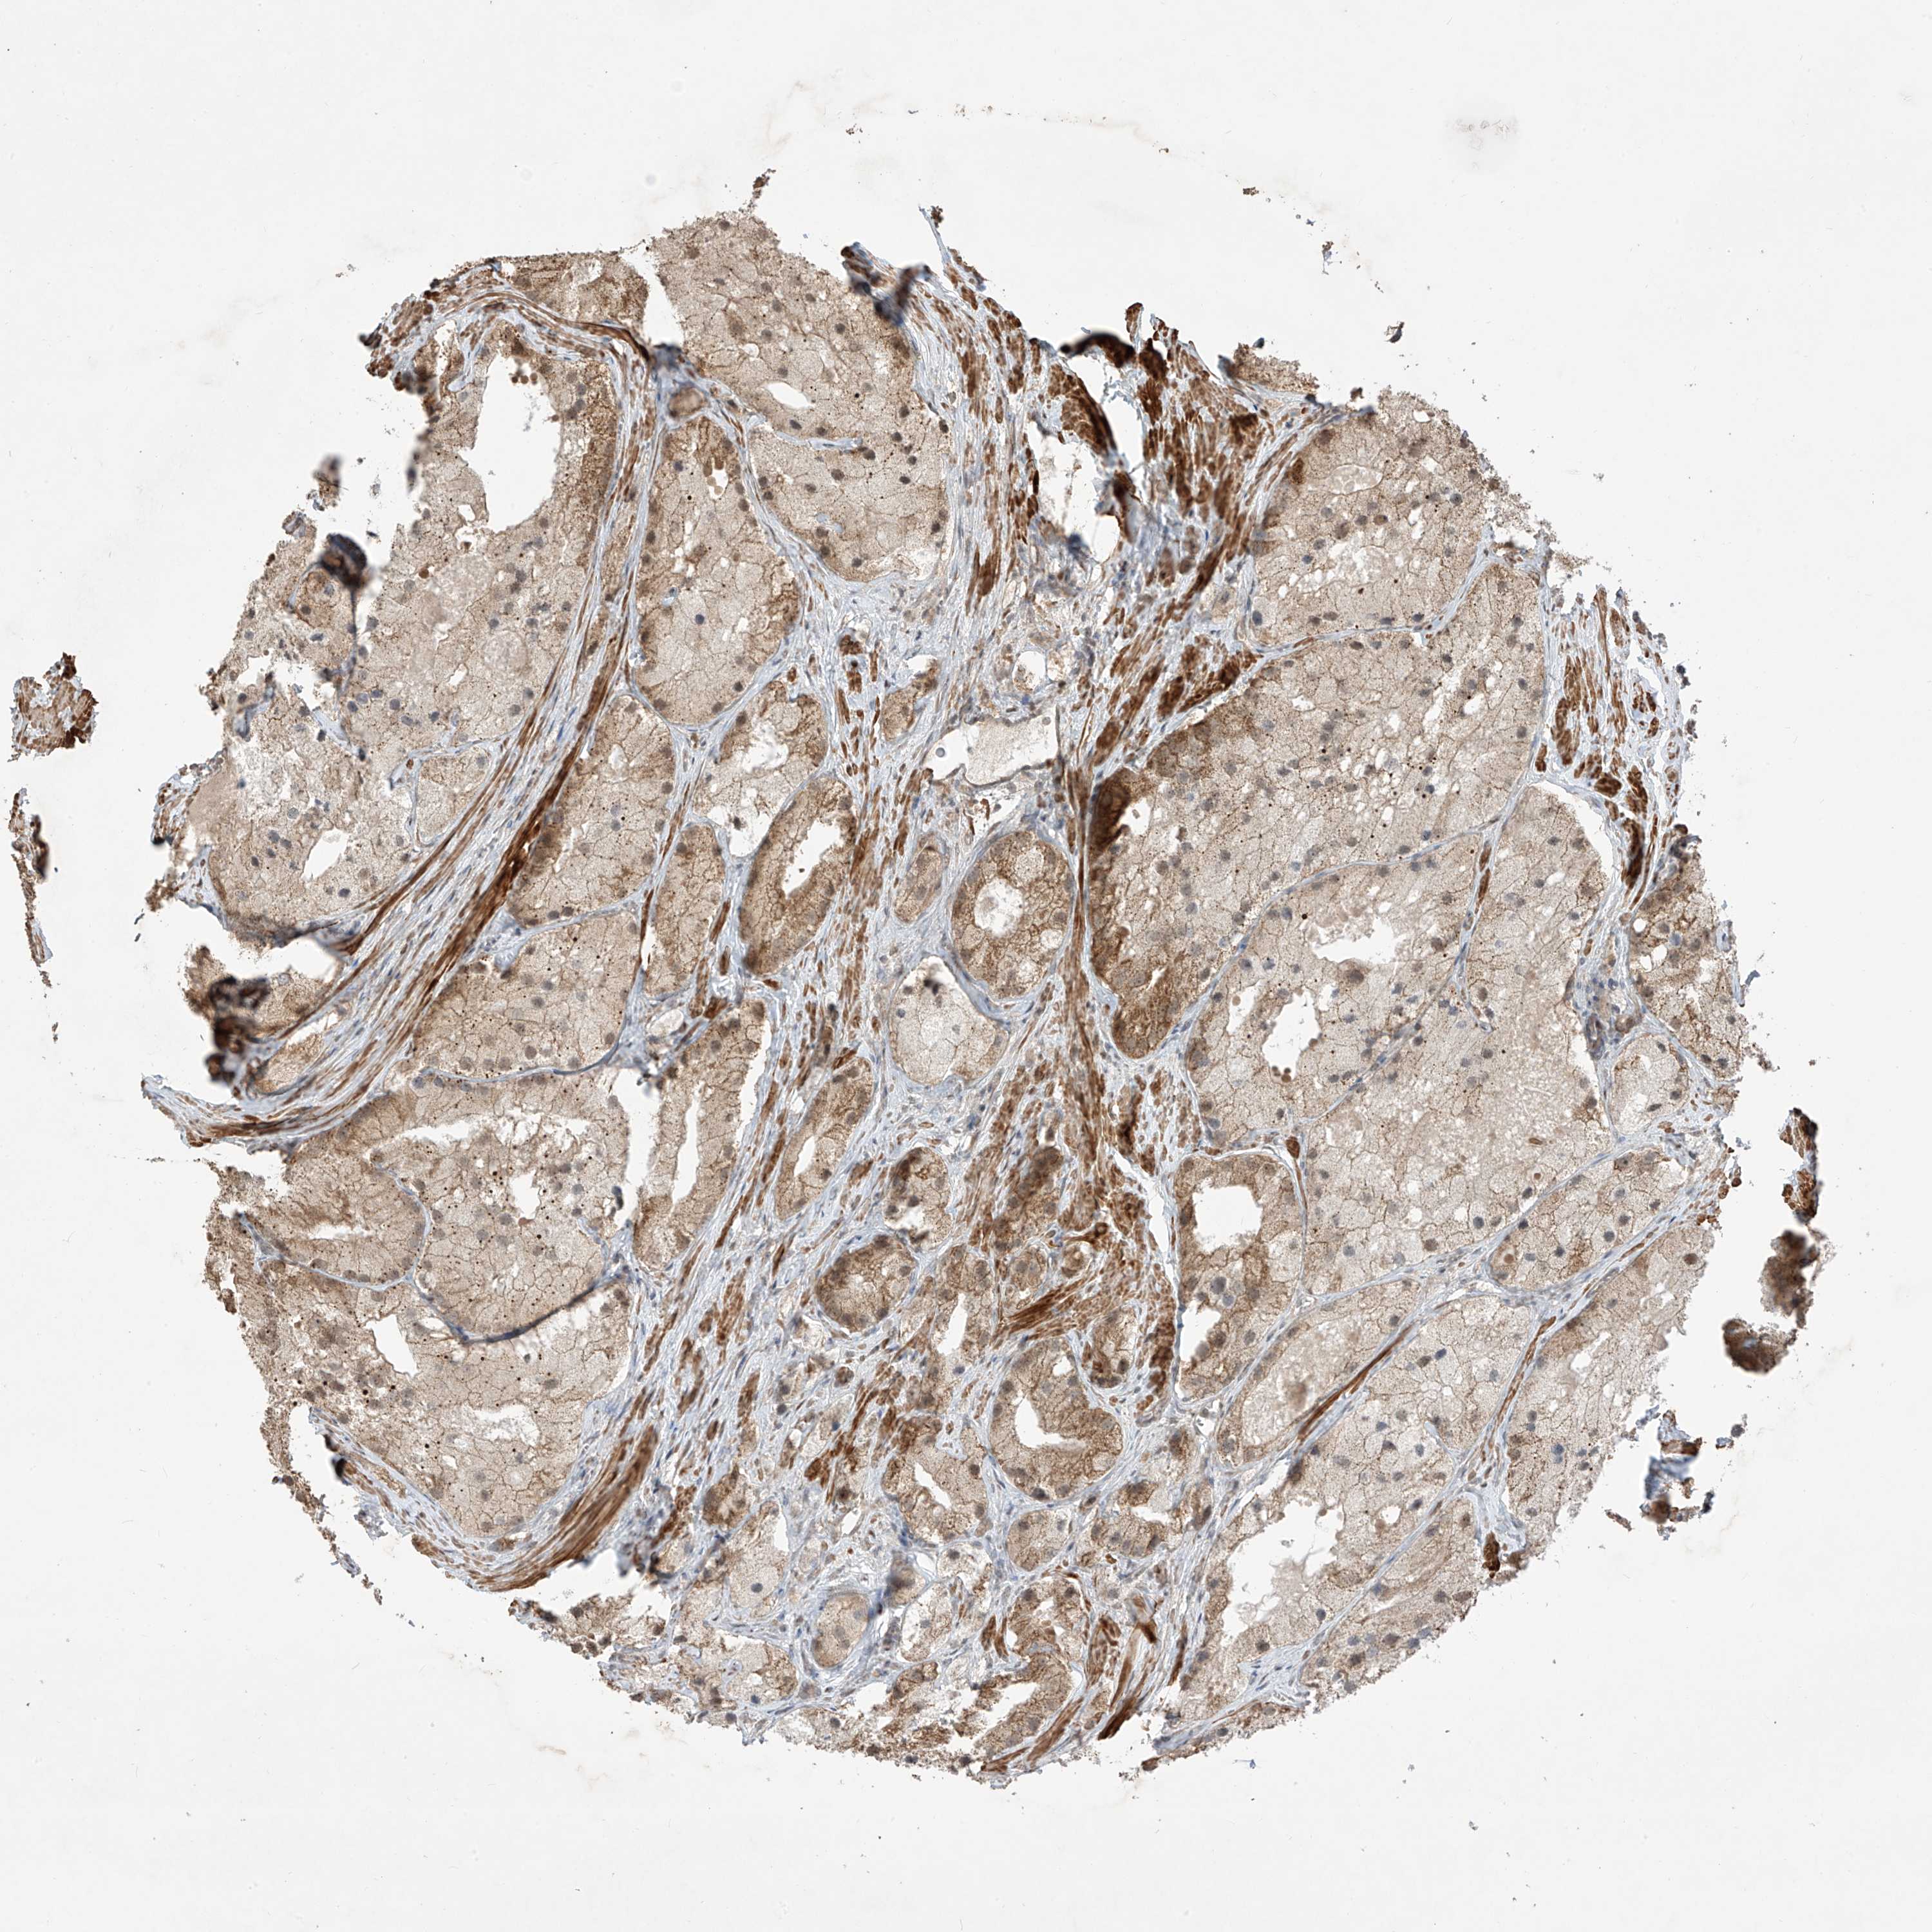

PROSTATE CANCER - Protein expressioni

A mouse-over function shows sample information and annotation data. Click on an image to view it in a full screen mode. Samples can be filtered based on level of antibody staining by selecting one or several of the following categories: high, medium, low and not detected. The assay and annotation is described here.

Antibody stainingi

Antibody staining in the annotated cell types in the current human tissue is reported as not detected, low, medium, or high, based on conventional immunohistochemistry profiling in selected tissues. This score is based on the combination of the staining intensity and fraction of stained cells.

Each image is clickable and will lead to virtual microscopy that enables deeper exploration of all samples and also displays staining intensity scores, fraction scores and subcellular localization as well as patient and tissue information for each sample.

Antibody HPA031804

Staining

High

Medium

Low

Not detected

Intensity

Strong

Moderate

Weak

Negative

Quantity

>75%

75%-25%

<25%

None

Location

Nuclear

Cytoplasmic/membranous

Cytoplasmic/membranous,nuclear

Adenocarcinoma, NOS

Adenocarcinoma, High grade

Adenocarcinoma, Low grade